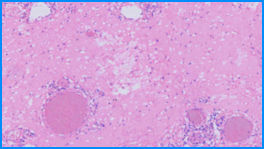

High Image Quality for Digital Pathology

KFBIO Digital Pathology Slide Scanner (PRO) is a world leader in the accuracy of movement, focus, and image processing, and its accurate whole slide imaging not only meets the requirements of digital slide viewing and operation but is also suitable for AI-assisted image analysis.

High Quality, 3 Colors Independent Processing

K-SCP color processing method helps restore the original color, saturation, color temperature, color contrast and other indicators to enhance images, as well as color compensation of different displays after imaging.

High Resolution, 0.5µm/pixel (20X), 0.25µm/pixel (40X)

It adopts top optical accessories. The light source, objective lens, camera, optical path and other accessories are comprehensively optimized. It greatly improves the optical resolution to directly observe the structure and details in the cell. The nucleus edge is sharp and the internal structure is clearly visible. The resolution distance can be as small as 0.125µm.